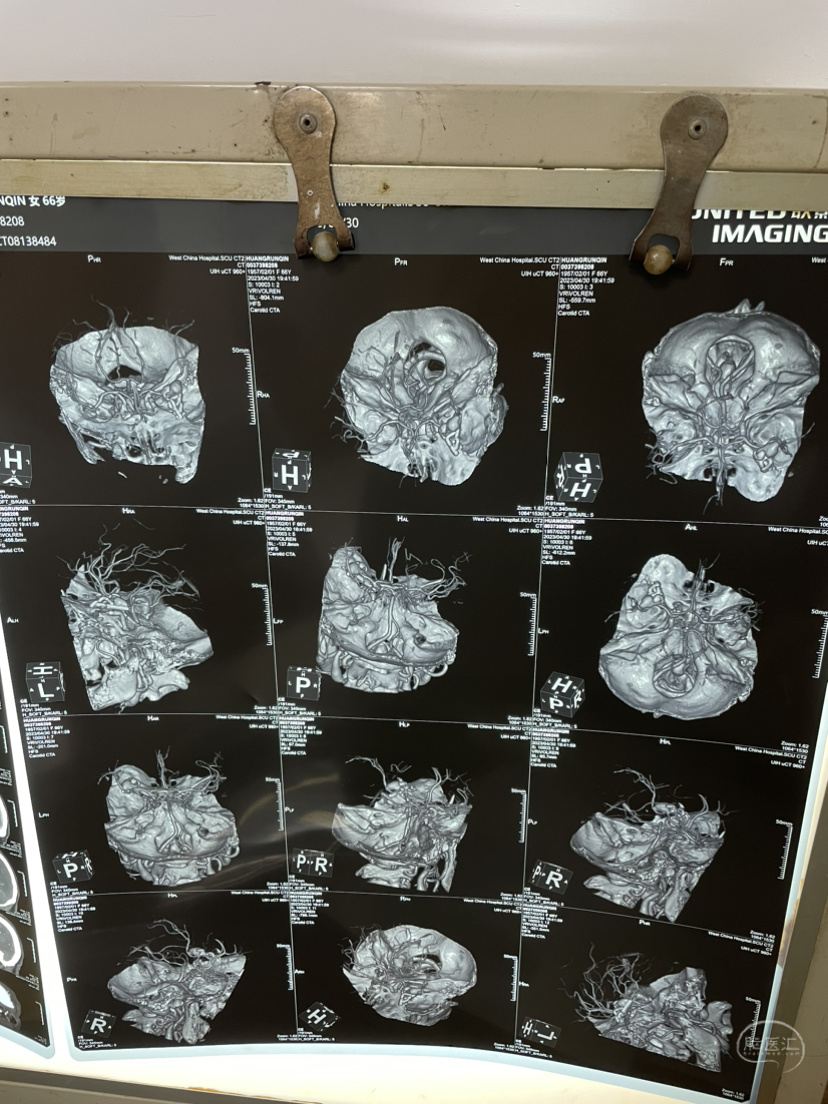

家属选择保守治疗,患者一直清醒!两个月前在华西行介入栓塞术,血肿吸收!

介入栓塞术后两个月来复查!患者清醒轮椅而来,言语稍含糊,右侧下肢肌力可大于三级,上肢一级!